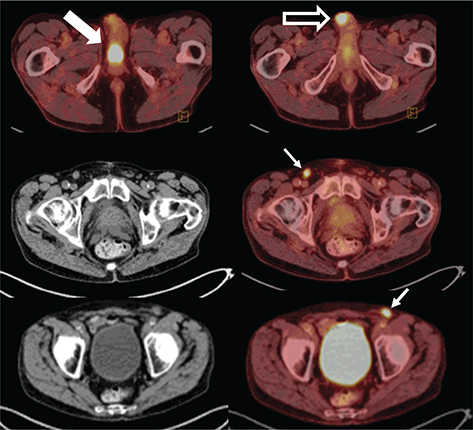

Fig 2

Figure 2. Penile base, surgical site, and lymph nodes. FDG PET/CT demonstrates hypermetabolic activity within the penile base (thick solid arrow), surgical site (thick open arrow), and bilateral inguinal lymph nodes (thin arrows). This patient was status post partial penectomy and chemotherapy for penile squamous cell carcinoma. Findings on PET/CT were consistent with progression of disease and poor response to chemotherapy.